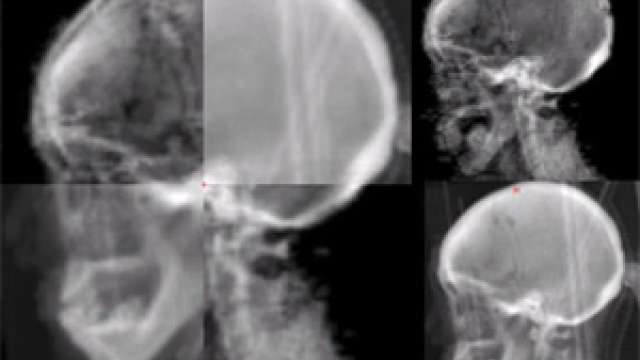

Brain & Spine Tumors

The UCLA Department of Radiation Oncology treats both malignant brain cancer and benign tumors.